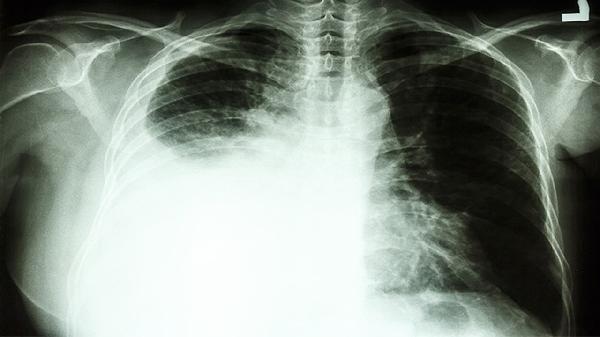

肺癌脑转移患者可遵医嘱使用奥希替尼片、吉非替尼片、埃克替尼片、阿来替尼胶囊、克唑替尼胶囊等靶向药物。肺癌脑转移通常由EGFR突变、ALK重排等基因异常导致,需通过基因检测明确突变类型后选择对应靶向药。